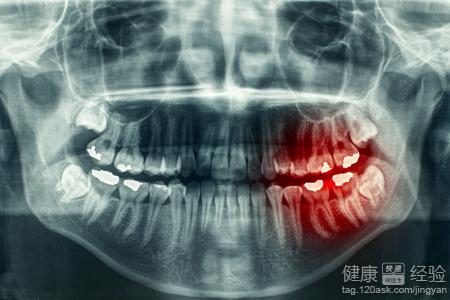

現實的生活當中,我們很多的患者對於自己的牙齒是不加以保護的在生活當中我們很容易讓自己患上了牙齒上面的一些疾病,那麼對於我們來說我們對於這些疾病來說並不是非常的了解,如果牙齒損壞的話對於我們來說是傷害比較大的,那麼對於患者來說,如果去醫院進行全冠修復的話,該怎麼做呢?下面就讓我來跟大家講一講該怎麼進行全冠修復牙齒。

1對於我們的患者朋友來說,家庭是生活當中如果要進行全冠修復牙齒的話。對於患者來說,可以去做牙根管治療。然後可以進行烤瓷鑲牙,對於患者來說,其實效果也是非常好的,患者應該注意。